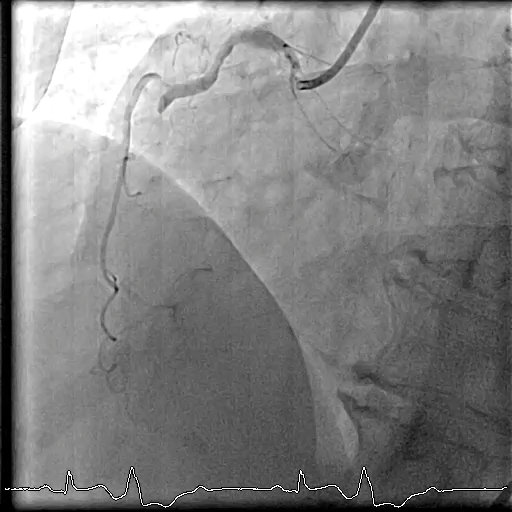

Right femoral approach with JL6/4, JR 6/4 diagnostic catheter show total occlusion mRCA, 30% stenosis at proximal-LAD, 90% stenosis at mid-LAD, 95% stenosis mid-LCx.

Cardiac catheterization was performed via right femoral approach with JL6/4, JR 6/4 diagnostic catheter show total occlusion mRCA, 30% stenosis at proximal-LAD, 90% stenosis at mid-LAD, 95% stenosis mid-LCx. PCI with JR 6/4. PCI to mid-RCA. GD: JR 6/4. Turntrac with Guidezilla to RCA. SC balloon 2.0x12 mm inflated mRCA up to 12 atm. Rapamycin eluting stent 3.0x18 mm deployed mRCA 12 atm with POT-PUFF sign technique. The final angiogram was acceptable result. After successful reperfusion of the right coronary artery, the premature ventricular complexes (PVCs) was subsides.